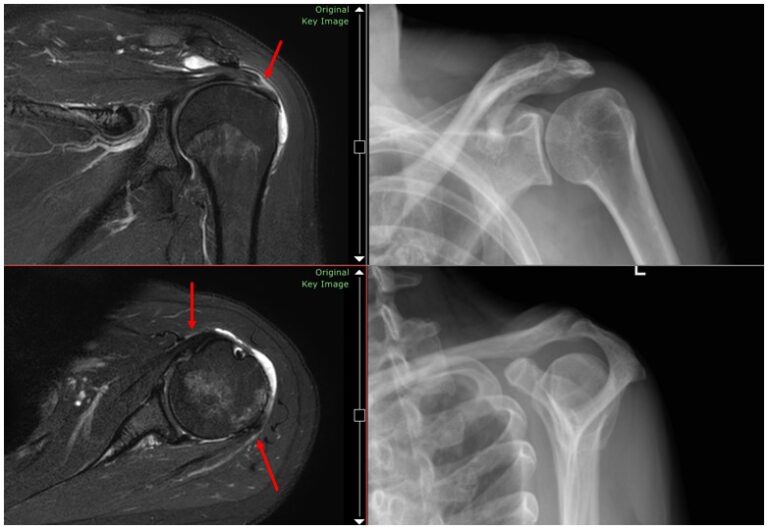

腱板は、一連の腱と筋肉を介して肩甲骨を腕の上部に接続します。腱板の損傷は一般的であり、腱板断裂関節症と呼ばれる一種の肩関節炎を引き起こす可能性があります。

腱板が断裂すると、肩の関節の圧力、動き、安定性が失われます。腱板が治癒できない場合、または断裂が大きすぎる場合、これらの損傷により軟骨や骨に損傷が生じ、腱板断裂関節症が引き起こされます。

この特定のタイプの肩関節炎は、治療せずに放置すると激しい痛みや衰弱を引き起こす可能性があり、これに対処している人は腕を頭の上に上げることが非常に困難になります。